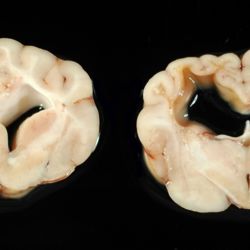

Pàgina anterior de 637 Pàgina següent 3181 total Bovine Specie: Bovine Organ: Bone Lesion: Scoliosis Lesion modifier: - Disease: Schmallenberg Files/Expedient: N-55/13 Position: 253 (1 views) Bovine Specie: Bovine Organ: Fetus Lesion: Scoliosis Lesion modifier: - Disease: Schmallenberg Files/Expedient: N-55/13 Position: 253 (1 views) Bovine Specie: Bovine Organ: Joint Lesion: Arthrogryposis Lesion modifier: - Disease: Schmallenberg Files/Expedient: N-55/13 Not viewed Canine Specie: Canine Organ: Brain Lesion: Malacia Lesion modifier: - Disease: - Files/Expedient: N-570/09 Not viewed Canine Specie: Canine Organ: Brain Lesion: Malacia Lesion modifier: - Disease: - Files/Expedient: N-570/09 Position: 253 (1 views) Pàgina anterior de 637 Pàgina següent Títol Select...Avian (Exotic) (110)Avian (Poultry) (76)Bovine (317)Canine (935)Caprine (47)Equine (257)Feline (326)Ferret (19)General (127)Marine mammal (22)Non-human primate (20)Ovine (328)Porcine (379)Rabbit (61)Reptile (38)Rodent (28)Wildlife (91) Format Select...- (60)Abomasum (37)Adrenal gland (10)Blood (7)Blood vessel (50)Body as a whole (19)Bone (57)Bone marrow (21)Brain (93)Cloaca (1)Diaphragm (2)Ear (5)Esophagus (39)Eye (16)Fetus (12)Gallbladder (23)Gizzard (2)Heart (265)Intestine (356)Joint (32)Kidney (443)Larynx (5)Liver (326)Lung (264)Lymph node (91)Mammary gland (10)Mediastinum (1)Muscle (22)Nasal cavity (22)Nerve (7)Omasum (5)Oral cavity (63)Ovary (14)Oviduct (8)Pancreas (7)Parathyroid (5)Penis (10)Peritoneum (65)Pharynx (9)Pituitary gland (6)Placenta (7)Prostate (8)Proventriculus (3)Reticulum (1)Rumen (28)Sinus (7)Skin (181)Spinal cord (15)Spleen (105)Stomach (125)Teeth (1)Testicle (11)Thoracic cavity (31)Thymus (13)Thyroid gland (5)Tongue (32)Tonsils (11)Trachea (11)Urethra (5)Urinay bladder (61)Uterus (27)Vagina (1)Vulva (1)Yolk sac (1) Cobertura Select...- (152)Abomasitis (26)Abscess (27)Acidosis (1)Adenocarcinoma (20)Adenoma (9)Aerosacculitis (6)Agenesis (1)Agnathia (1)Alopecia (7)Amyloidosis (12)Aneurysm (6)Angiectasis (1)Anthracosis (1)Arteritis (11)Arthritis (15)Arthrogryposis (6)Artifact (4)Ascites (13)Atelectasis (8)Atherosclerosis (5)Atresia (1)Atrial septal defect (2)Atrophy (10)Autolysis (7)Bronchitis (6)Bronchopneumonia (26)Cachexia (2)Carcinoma (103)Cardiomyopathy (19)Cellulitis (2)Chemodectoma (4)Cholangiohepatitis (4)Cholangitis (19)Cholecystitis (4)Cholestasis (5)Chondrodysplasia (2)Chondrosarcoma (2)Chronic passive congestion (13)Chylothorax (2)Cirrhosis (6)Coelomitis (3)Coenurus cerebralis (4)Colitis (40)Congestion (17)Conjunctivitis (5)Coronitis (3)Cryptorchidism (3)Cyst (25)Cystitis (24)Dermatitis (69)Diaphragmatic hernia (4)Dilation (28)Discospondylitis (1)Disseminated intravascular coagulation (7)Dyschondroplasia (1)Dysplasia (29)Ectopia cordis (1)Ectopic ureter (1)Edema (55)Emphysema (5)Encephalitis (5)Endocardiosis (14)Endocarditis (26)Endometritis (5)Enteritis (118)Enterolith (6)Epulis (3)Esophagitis (14)Fasciitis (1)Fibrosis (7)Fibrous osteodystrophy (8)Fistula (1)Folliculitis (3)Fracture (2)Gastritis (34)Gingivitis (5)Glioma (8)Glomerulonephritis (21)Glossitis (25)Glycogenosis (1)Gout (8)Granuloma (2)Granulosa cell tumor (4)Hemangioma (9)Hemangiosarcoma (46)Hematoma (8)Hemoglobinuria (2)Hemopericardium (12)Hemoperitoneum (2)Hemorrhage (100)Hemosiderosis (7)Hemothorax (2)Hepatitis (78)Hernia (11)Histiocytosis (3)Hydatid cyst (11)Hydrocephalus (9)Hydrometra (1)Hydronephrosis (22)Hydropericardium (6)Hydrothorax (3)Hydroureter (5)Hyperkeratosis (8)Hyperostosis (4)Hyperplasia (37)Hypertrophy (9)Hypopigmentation (1)Hypoplasia (7)Hypopyon (1)Impaction (6)Infarction (63)Insulinoma (6)Intussusception (5)Jaundice (17)Laminitis (2)Laryngitis (2)Leiomyoma (5)Leukemia (13)Lipidosis (36)Lipoma (7)Lymphadenitis (45)Lymphadenopathy (7)Lymphangiectasia (6)Lymphangitis (5)Lymphoma (221)Malacia (11)Malignant melanoma (15)Mast cell tumor (11)Mastitis (8)Megaesophagus (2)Melanosis (3)Melena (4)Meningioma (6)Meningitis (6)Meningocele (2)Meningoencephalitis (5)Mesothelioma (5)Methemoglobinemia (2)Mineralization (10)Mucocele (5)Mucometra (1)Multilobular bone tumor (1)Mummification (3)Myelofibrosis (1)Myocarditis (4)Myositis (5)Necrosis (81)Nephritis (113)Nephroblastoma (6)Nephrosclerosis (1)Nephrosis (14)Neuritis (1)Obstruction (13)Omasitis (4)Omphalitis (1)Omphalophlebitis (7)Orchitis (4)Osteoarthrosis (5)Osteomyelitis (9)Otitis (2)Palatoschisis (3)Pancreatitis (3)Panniculitis (3)Papilloma (7)Parakeratosis (14)Patent ductus arteriosus (6)Peliosis hepatis (1)Perforation (17)Pericarditis (35)Peritonitis (39)Persistent right aortic arch (1)Pharyngitis (2)Pheochromocytoma (2)Phlebitis (2)Placentitis (6)Pleuritis (21)Pleuropneumonia (24)Pneumonia (109)Pneumothorax (3)Polycystosis (14)Polyp (5)Polyserositis (6)Posthitis (1)Proctitis (4)Prolapse (3)Prostatitis (3)Proventriculitis (1)Pyelonephritis (24)Pyometra (6)Pyothorax (4)Rhinitis (11)Rumenitis (6)Rupture (24)Salpingitis (3)Sarcoma (57)Sclerosis (1)Scoliosis (2)Seminoma (2)Sequestrum (2)Serous atrophy (14)Sinusitis (7)Splenitis (14)Splenomegaly (9)Spondylitis (6)Spondylosis (1)Stenosis (9)Stomatitis (32)Tenosynovitis (2)Teratoma (3)Thricobezoar (2)Thrombosis (16)Tonsilitis (4)Torsion (13)Tracheitis (4)Tympany (7)Typhlitis (8)Typhlocolitis (4)Ulcer (43)Urethritis (1)Urolithiasis (36)Uroperitoneum (1)Uveitis (1)Vasculitis (15)Ventricular septal defect (3)Volvulus (11) Matèria Select... - (14)- (1653)- (152)Abomasitis - Catarrhal (2)Abomasitis - Catarrhal-hemorrhagic (1)Abomasitis - Chronic (1)Abomasitis - Fibrinous-necrotizing (2)Abomasitis - Hyperplasic (5)Abomasitis - Hyperplasic - Chronic (1)Abomasitis - Necrotic (1)Abomasitis - Necrotizing (2)Abomasitis - Ulcerative (5)Adenocarcinoma (9)Aerosacculitis - Granulomatous (1)Amyloidosis - Chronic (1)Arteritis - Necrotic (2)Arteritis - Necrotizing (1)Arthritis - Chronic (4)Arthritis - Fibrinous-purulent (3)Arthritis - Serous (4)Arthritis - Subacute (1)Ascites - Serous (1)Atrophy - Serous (1)Bronchitis - Catarrhal (3)Bronchitis - Suppurative (1)Bronchopneumonia - Catarrhal-purulent (17)Bronchopneumonia - Fibrinous (1)Bronchopneumonia - Granulomatous (1)Bronchopneumonia - Purulent (1)Bronchopneumonia - Suppurative (5)Carcinoma - Adenocarcinoma (33)Carcinoma - Adenocarcinoma - Hepatocellular (2)Carcinoma - Adenocarcinoma - Mucinous (1)Carcinoma - Basosquamous (1)Carcinoma - Cholangiocellular (3)Carcinoma - Hepatocellular (4)Carcinoma - Metastatic (3)Carcinoma - Squamous cell carcinoma (13)Carcinoma - Transitional cell (2)Cardiomyopathy - Dilated (13)Cardiomyopathy - Hypertrophic (6)Cellulitis - Necrotizing (1)Cholangitis - Chronic (8)Cholangitis - Hyperplasic (3)Cholecystitis - Fibrinous-necrotizing (1)Coelomitis - Fibrinous (1)Coelomitis - Granulomatous (1)Colitis - Catarrhal (3)Colitis - Catarrhal-hemorrhagic (1)Colitis - Fibrinous (1)Colitis - Fibrinous-necrotizing (1)Colitis - Fibrinous-necrotizing (Diphtheritic) (6)Colitis - Granulomatous (2)Colitis - Hemorrhagic (4)Colitis - Hemorrhagic-necrotizing (3)Colitis - Necrotizing (2)Colitis - Ulcerative (6)Congestion - Chronic (2)Conjunctivitis - Hyperplasic (1)Conjunctivitis - Purulent (3)Coronitis - Ulcerative (1)Cystitis - Chronic (3)Cystitis - Fibrinous (1)Cystitis - Fibrinous-necrotizing (1)Cystitis - Follicular (1)Cystitis - Hemorrhagic (6)Cystitis - Hemorrhagic-ulcerative (1)Cystitis - Necrotizing (9)Cystitis - Perforated (1)Dermatitis - Granulomatous (14)Dermatitis - Hyperkeratotic (10)Dermatitis - Hyperplasic (proliferative) (1)Dermatitis - Hyperplastic (10)Dermatitis - Necrotizing (4)Dermatitis - Pustular (4)Dermatitis - Ulcerative (2)Dilation - Chronic (1)Discospondylitis - Necrotizing (1)Dysplasia - Follicular (5)Edema - Interstitial (6)Emphysema - Interstitial (1)Encephalitis - Granulomatous (1)Encephalitis - Nonsuppurative (1)Endocardiosis - Mitral (7)Endocardiosis - Mitral - Chronic (5)Endocarditis - Valvular (6)Endocarditis - Valvular - Mitral (7)Endocarditis - Valvular - Pulmonic (1)Endocarditis - Valvular - Subacute (1)Endocarditis - Valvular - Subaortic (5)Endocarditis - Valvular - Tricuspid (4)Endometritis - Purulent (3)Endometritis - Purulent-hemorrhagic (2)Enteritis - Catarrhal (23)Enteritis - Catarrhal - Acute (1)Enteritis - Catarrhal-hemorrhagic (5)Enteritis - Catarrhal-hemorrhagic - Acute (2)Enteritis - Fibrinous (16)Enteritis - Fibrinous - Acute (3)Enteritis - Fibrinous-necrotizing (7)Enteritis - Granulomatous (14)Enteritis - Granulomatous - Chronic (1)Enteritis - Granulomatous - Multifocal (1)Enteritis - Hemorrhagic (17)Enteritis - Hemorrhagic - Acute (1)Enteritis - Hemorrhagic-necrotizing (1)Enteritis - Hyperplasic (proliferative) (4)Enteritis - Necrotizing (4)Enteritis - Necrotizing - Acute (1)Enteritis - Necrotizing - Hemorrhagic (1)Enteritis - Necrotizing-ulcerative (2)Enteritis - Ulcerative (1)Enteritis - Ulcerative-hemorrhagic (1)Esophagitis - Erosive-ulcerative (6)Esophagitis - Necrotizing (4)Esophagitis - Ulcerative (1)Esophagitis - Ulcerative-necrotizing (1)Fasciitis - Fibrinous-purulent (1)Folliculitis - Purulent (2)Gastritis - Catarrhal (2)Gastritis - Chronic (1)Gastritis - Follicular (1)Gastritis - Hemorrhagic (2)Gastritis - Hemorrhagic-necrotizing (1)Gastritis - Hypertrophic (2)Gastritis - Inclusion bodies (1)Gastritis - Mineralization (1)Gastritis - Mycotic (1)Gastritis - Necrotizing (2)Gastritis - Ulcerative (6)Gastritis - Uremic (3)Gingivitis - Erosive (2)Gingivitis - Hyperplasic (proliferative) (1)Gingivitis - Necrotizing (1)Glomerulonephritis - Chronic (7)Glomerulonephritis - Membranoproliferative (3)Glomerulonephritis - Membranoproliferative - Chronic (1)Glomerulonephritis - Membranous (3)Glomerulonephritis - Membranous - Chronic (1)Glomerulonephritis - Proliferative (2)Glomerulonephritis - Subacute (1)Glossitis - Erosive (2)Glossitis - Granulomatous (6)Glossitis - Hyperplasic (1)Glossitis - Hyperplasic (proliferative) (2)Glossitis - Hyperplastic (1)Glossitis - Necrotizing (2)Glossitis - Necrotizing - Focal (1)Glossitis - Ulcerative (6)Glossitis - Ulcerative - Multifocal (1)Glossitis - Ulcerative - Subacute (1)Glycogenosis (1)Granuloma - Eosinophilic (1)Hemangiosarcoma - Metastatic (2)Hemorrhage - Acute (1)Hemorrhage - Subcapsular (3)Hepatitis - Abscess (9)Hepatitis - Acute (3)Hepatitis - Chronic (4)Hepatitis - Chronic interstitial (6)Hepatitis - Granulomatous (7)Hepatitis - Interstitial - Multifocal (1)Hepatitis - Interstitial - Subacute (1)Hepatitis - Necrotizing (17)Hepatitis - Necrotizing - Acute (2)Hepatitis - Necrotizing - Hemorrhagic (1)Hepatitis - Necrotizing - Subacute (1)Hepatitis - Pyogranulomatous (7)Hepatitis - Subacute (4)Hydronephrosis - Chronic (1)Hydropericardium - Chronic (1)Hyperplasia - Erythroid (1)Hyperplasia - Lymphoid (3)Hyperplasia - Myeloid (1)Hyperplasia - Nodular (8)Hypertrophy - Concentric (2)Hypertrophy - Eccentric (3)Infarction - Acute (17)Infarction - Acute - Multifocal (2)Infarction - Chronic (5)Infarction - Chronic - Multifocal (1)Infarction - Subacute (18)Infarction - Subacute - Focal (2)Laminitis - Chronic (2)Laryngitis - Necrotic (1)Laryngitis - Necrotizing (1)Leukemia - Lymphoid leukemia (2)Leukemia - Non-lymphoid leukemia (6)Lipidosis - Multifocal (1)Lipidosis - Panlobular (1)Lipidosis - Panlobular - Generalized (2)Lymphadenitis - Granulomatous (24)Lymphadenitis - Granulomatous - Chronic (3)Lymphadenitis - Hemorrhagic (1)Lymphadenitis - Necrotizing (5)Lymphadenitis - Necrotizing (caseous) (11)Lymphangitis - Granulomatous (1)Lymphangitis - Purulent (1)Lymphangitis - Ulcerative (1)Lymphoma - Alimentary lymphoma (7)Lymphoma - Cutaneous lymphoma (6)Lymphoma - Lymphosarcoma (2)Lymphoma - Mediastinal lymphoma (1)Lymphoma - Multicentric lymphoma (29)Malignant melanoma - Malignant (1)Malignant melanoma - Metastatic (1)Mast cell tumor - Metastatic (1)Mastitis - Fibrinous-purulent (2)Mastitis - Necrotic (1)Mastitis - Purulent (3)Mastitis - Suppurative (1)Meningitis - Fibrinous-purulent (2)Meningitis - Purulent (4)Meningoencephalitis - Necrotizing (3)Meningoencephalitis - Nonsuppurative (2)Mineralization - Metastatic (4)Myocarditis - Fibrous - Chronic (1)Myocarditis - Granulomatous (1)Myositis - Purulent (2)Necrosis - Acute (1)Necrosis - Cortical (5)Necrosis - Follicular (1)Necrosis - Papillary (8)Necrosis - Papillary - Acute (3)Necrosis - Subacute (3)Necrosis - Tubular (6)Nephritis - Embolic (2)Nephritis - Embolic suppurative (7)Nephritis - Granulomatous (27)Nephritis - Granulomatous - Chronic (1)Nephritis - Granulomatous - Multifocal (1)Nephritis - Interstitial (6)Nephritis - Interstitial - Acute (4)Nephritis - Interstitial - Chronic (41)Nephritis - Interstitial - Subacute (12)Nephritis - Purulent (7)Nephritis - Purulent - Acute (2)Nephritis - Purulent - Multifocal (3)Nephrosis - Cholemic (3)Nephrosis - Hemoglobinuric (10)Omasitis - Fibrinous-necrotizing (1)Omasitis - Hyperkeratotic (1)Omasitis - Necrotizing (2)Omphalophlebitis - Fibrinous-purulent (2)Omphalophlebitis - Purulent (3)Orchitis - Necrotizing (1)Osteomyelitis - Necrotizing (7)Osteomyelitis - Purulent (2)Otitis - Necrotizing (1)Otitis - Proliferative (1)Pancreatitis - Acute (1)Pancreatitis - Chronic (1)Pancreatitis - Granulomatous (1)Panniculitis - Fibrinous-purulent (1)Panniculitis - Necrotic (1)Panniculitis - Parasitic (1)Perforation - Acute (2)Pericarditis - Fibrinous (19)Pericarditis - Fibrinous - Subacute (1)Pericarditis - Fibrinous-necrotizing (1)Pericarditis - Fibrinous-purulent (3)Pericarditis - Fibrous (1)Pericarditis - Fibrous - Chronic (1)Pericarditis - Gangrenous (6)Pericarditis - Granulomatous (1)Pericarditis - Granulomatous - Chronic (2)Peritonitis - Acute (1)Peritonitis - Fibrinous (11)Peritonitis - Fibrinous - Subacute (1)Peritonitis - Fibrinous-purulent (5)Peritonitis - Fibrous (3)Peritonitis - Granulomatous (6)Peritonitis - Purulent (1)Peritonitis - Purulent-hemorrhagic (1)Peritonitis - Pyogranulomatous (3)Pharyngitis - Fibrinous-necrotizing (1)Pharyngitis - Ulcerative (1)Pheochromocytoma - Metastatic (1)Phlebitis - Purulent (1)Placentitis - Fibrinous-necrotizing (1)Placentitis - Necrotic (1)Placentitis - Necrotizing (1)Pleuritis - Chronic (1)Pleuritis - Fibrinous (3)Pleuritis - Fibrinous-purulent (2)Pleuritis - Fibrous (2)Pleuritis - Granulomatous (3)Pleuritis - Hyperplastic (2)Pleuritis - Purulent (2)Pleuritis - Pyogranulomatous (1)Pleuropneumonia - Fibrinous (13)Pleuropneumonia - Fibrinous-necrotizing (5)Pleuropneumonia - Granulomatous (2)Pleuropneumonia - Hemorrhagic-necrotizing (4)Pneumonia - Aspiration (11)Pneumonia - Bronchointerstitial (4)Pneumonia - Bronchointerstitial - Subacute (1)Pneumonia - Embolic (5)Pneumonia - Granulomatous (37)Pneumonia - Granulomatous - Multifocal (4)Pneumonia - Hemorrhagic-necrotizing (2)Pneumonia - Interstitial (7)Pneumonia - Interstitial - Acute (8)Pneumonia - Interstitial - Chronic (6)Pneumonia - Interstitial - Subacute (15)Pneumonia - Necrotizing (2)Pneumonia - Pyogranulomatous (2)Pneumonia - Verminous (5)Polyserositis - Fibrinous (6)Polyserositis - Fibrous (1)Proctitis - Fibrinous-necrotizing (1)Proctitis - Parasitic (2)Prostatitis - Purulent (1)Pyelonephritis - Acute (2)Pyelonephritis - Chronic (3)Rhinitis - Catarrhal (2)Rhinitis - Fibrinous (1)Rhinitis - Granulomatous (4)Rhinitis - Purulent (3)Rumenitis - Acute (1)Rumenitis - Erosive (1)Rumenitis - Necrotizing (1)Rupture - Acute (3)Sarcoma - Fibrosarcoma (12)Sarcoma - Hemangiosarcoma (11)Sarcoma - Histiocytic (7)Sarcoma - Metastatic (1)Sarcoma - Multilobular tumor of bone (1)Sequestrum - Chronic (2)Sinusitis - Suppurative (1)Splenitis - Granulomatous (8)Splenitis - Granulomatous - Chronic (1)Splenitis - Necrotizing (3)Splenitis - Necrotizing (caseous) (2)Spondylitis - Necrotizing (2)Stenosis - Intestinal (1)Stenosis - Valvular - Subaortic (4)Stomatitis - Erosive (12)Stomatitis - Erosive-ulcerative (3)Stomatitis - Fibrinous-necrotizing (1)Stomatitis - Fibrinous-necrotizing (Diphtheritic) (1)Stomatitis - Granulomatous (1)Stomatitis - Hyperplasic (1)Stomatitis - Hyperplasic (proliferative) (1)Stomatitis - Necrotizing (2)Stomatitis - Ulcerative (5)Stomatitis - Ulcerative - Multifocal (1)Stomatitis - Ulcerative-necrotizing (1)Tonsilitis - Necrotizing (4)Torsion - Acute passive hyperemia (5)Tracheitis - Catarrhal (3)Tracheitis - Fibrinous (1)Tracheitis - Granulomatous (1)Typhlitis - Catarrhal (1)Typhlitis - Fibrinous-necrotizing (2)Typhlitis - Hemorrhagic (2)Typhlitis - Ulcerative-hemorrhagic (1)Typhlocolitis - Fibrinous-necrotizing (2)Typhlocolitis - Proliferative (1)Ulcer - Chronic (6)Ulcer - Multifocal (2)Ulcer - Mycotic (1)Ulcer - Perforated (6)Urethritis - Hemorrhagic (1)Urolithiasis - Chronic (2)Uveitis - Granulomatous (1)Vasculitis - Granulomatous (1)Vasculitis - Necrotizing (1) Editor Select...- (1970)Acidosis (2)Actinobacillosis (Pleuropneumonia) (11)Aelurostrongylosis (2)African horse sickness (13)African swine fever (14)Alopecia X (1)Anaplasmosis (4)Anthrax (2)Aortic thromboembolism (feline) (7)Ascariasis (15)Aspergillosis (18)Atopic dermatitis (1)Atrophic rhinitis (3)Babesiosis (6)Blackhead (1)Bluetongue (11)Border disease (2)Bovine viral diarrhea (21)Brucellosis (2)Candidiasis (5)Canine distemper (14)Caprine arthritis-encephalitis (2)Capture myopathy (1)Cardiac insufficiency (17)Caseous lymphadenitis (7)Chlamydiosis (2)Classical swine fever (19)Clostridiosis (19)Coccidiosis (9)Coenurosis (4)Colibacillosis (21)Contagious ecthyma (7)Copper toxicosis (11)Cowdriosis (Heartwater) (3)Cryptococcosis (3)Cryptosporidiosis (2)Cysticercosis (23)Demodicosis (1)Diabetes (1)Dicrocoeliosis (5)Dictyocaulosis (4)Dirofilariasis (7)Discoid lupus erythematosus (3)Echinococcosis (17)Edema disease (7)Egg drop syndrome (1)Encephalitozoonosis (5)Enterotoxemia (1)Enzootic bovine leukosis (46)Epitheliogenesis imperfecta (3)Equine rhinopneumonitis (2)Equine verminous arteritis (strongylosis) (7)Erysipelas (5)Exudative epidermitis (7)Fasciolasis (11)Feline eosinophilic dermatoses (1)Feline hepatic lipidosis (8)Feline histiocytosis (4)Feline infectious peritonitis (38)Feline leukemia (4)Feline lower urinary tract disease (3)Feline panleukopenia (16)Feline viral rhinotracheitis (1)Flea allergy dermatitis (1)Foot and mouth disease (2)Gasterophilosis (4)Glasser's disease (15)Gousiekte (4)Gout (6)Haemonchosis (9)Hemolytic anemia (4)Hemorrhagic diathesis (1)Hepatic insufficiency (11)Hepatosis dietetica (7)Herpesvirosis (6)Hyperadrenocorticism (7)Hyperparathyroidism (10)Hypertrophic osteopathy (6)Hypervitaminosis D (1)Hypodermosis (1)Inclusion body hepatitis (4)Infectious bovine rhinotracheitis (5)Infectious bronchitis (5)Infectious canine hepatitis (13)Influenza (4)Juvenile nephropathy (8)Lamb dysentery (4)Leishmaniasis (28)Leptospirosis (1)Leukosis (5)Listeriosis (4)Lumpy skin disease (3)Maedi-visna (4)Malignant catarrhal fever (12)Mange (6)Mannheimiosis (5)Marek's disease (7)Metabolic bone disease (2)Mucoid enteropathy (5)Mulberry heart disease (5)Myasis (1)Mycobacteriosis (22)Mycosis fungoides (6)Myxomatosis (3)Necrobacillosis (5)Neonatal isoerythrolysis (6)Nocardiosis (4)Oestrosis (2)Onchocerciasis (1)Osteochondrosis (1)Ostertagiosis (6)Ovine pulmonary adenocarcinoma (5)Oxyuriasis (1)Pacheco's disease (4)Papillomatosis (6)Paratuberculosis (18)Parvovirosis (17)Pasteurellosis (11)Pemphigus foliaceus (1)Periodontal disease (1)Polioencephalomalacia of ruminants (4)Polyarteritis nodosa (3)Polycystic kidney disease (13)Porcine circovirosis (11)Porcine dermatitis and nephropathy syndrome (9)Porcine proliferative enteropathy (4)Porcine reproductive and respiratory syndrome (6)Porcine stress syndrome (1)Pox (13)Pregnancy toxemia (3)Proventricular dilatation disease (2)Pseudotuberculosis (yersiniosis) (2)Psittacine beak and feather disease (PBFD) (5)Pyoderma (4)Q fever (4)Rabbit hemorrhagic disease (2)Renal insufficiency (12)Reticuloendotheliosis (2)Rhodococcosis (1)Rickets (1)Rinderpest (2)Salmonellosis (34)Sarcosporidiosis (2)Schmallenberg (7)Septicemia (23)Spirocercosis (11)Streptococcosis (5)Strongylosis (1)Swine dysentery (5)Systemic coronavirosis (5)Tetralogy of Fallot (5)Theileriosis (13)Thromboembolism (5)Toxoplasmosis (11)Transmissible viral proventriculitis (1)Traumatic reticuloperitonitis (3)Traumatism (16)Tuberculosis (58)Ulcerative lymphangitis (1)Uremic syndrome (20)Viral arthritis (6)White muscle disease (9)Wobbler syndrome (2)Xanthomatosis (1)Zygomycosis (4) Idioma Select...- (1180)Bacterial (501)Degeneration (106)Fungal (46)Hemodynamic (112)Idiopathic (22)Inflammation (58)Malformation (88)Neoplasia (343)Nutritional (41)Parasitic (243)Physical/Chemical (93)Toxic (44)Viral (304) Ítem destacat Canine Intervertebral disk herniation in T6-T7 and T7-T8 with medullary compression. There is also ventral protrusion with spondylosis. Other intervertebral…